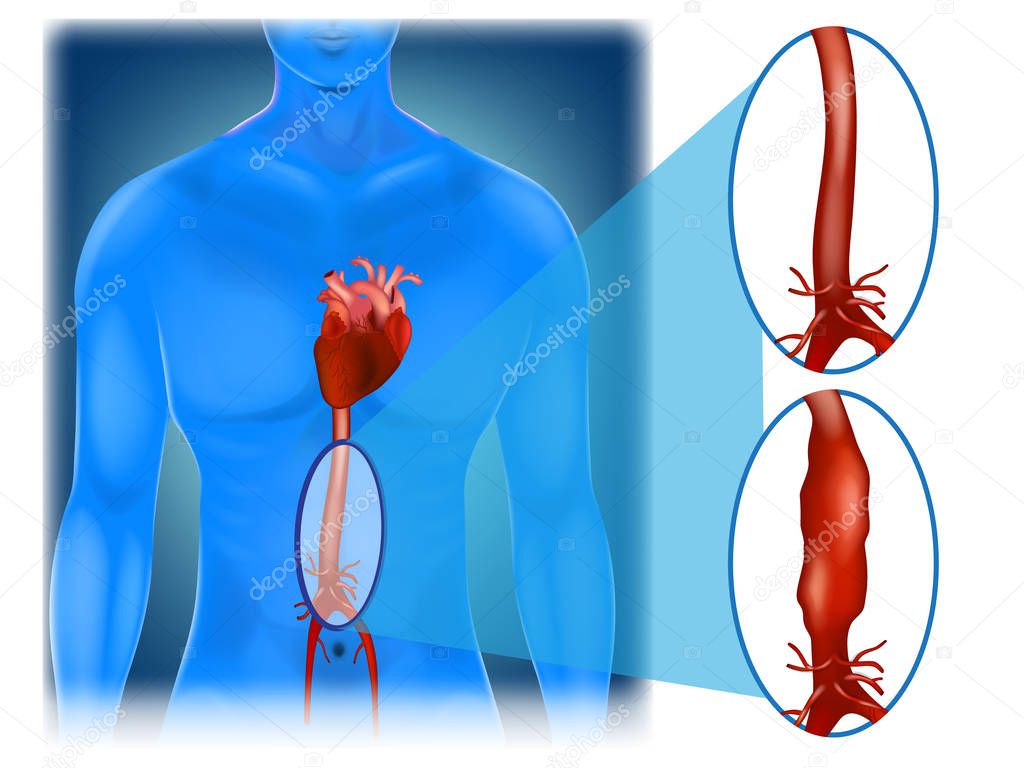

Un aneurisma aórtico abdominal es un agrandamiento de la parte baja de la aorta que se extiende a.

aneurisma de la aorta abdominal La aorta va desde el corazón hasta el. Recibe sangre con gran contenido en oxígeno. Cirugía vascularrupturas de aneurisma de la aorta abdominal: La cirugía de reparación abierta de aneurisma aórtico abdominal (aaa) se realiza para arreglar una parte dilatada de la aorta. Si tienes un aneurisma de la aorta abdominal en expansión, podrías notar lo siguiente: La incidencia de aaai en. En este artículo examen físico pruebas de detección y de diagnóstico ¿quiénes deben someterse a un examen de detección de aneurisma de aorta torácica? Los aneurismas aórticos aneurismas aórticos la aorta, que mide alrededor de 2,5 cm de calibre o diámetro, es la arteria más grande del cuerpo.

ABDOMINAL AORTIC ANEURYSMS Medical Yukti

Source: medicalyukti.blogspot.com

Aneurisma aórtico abdominal localización y apariencia. 2022

Source: www.deperu.com